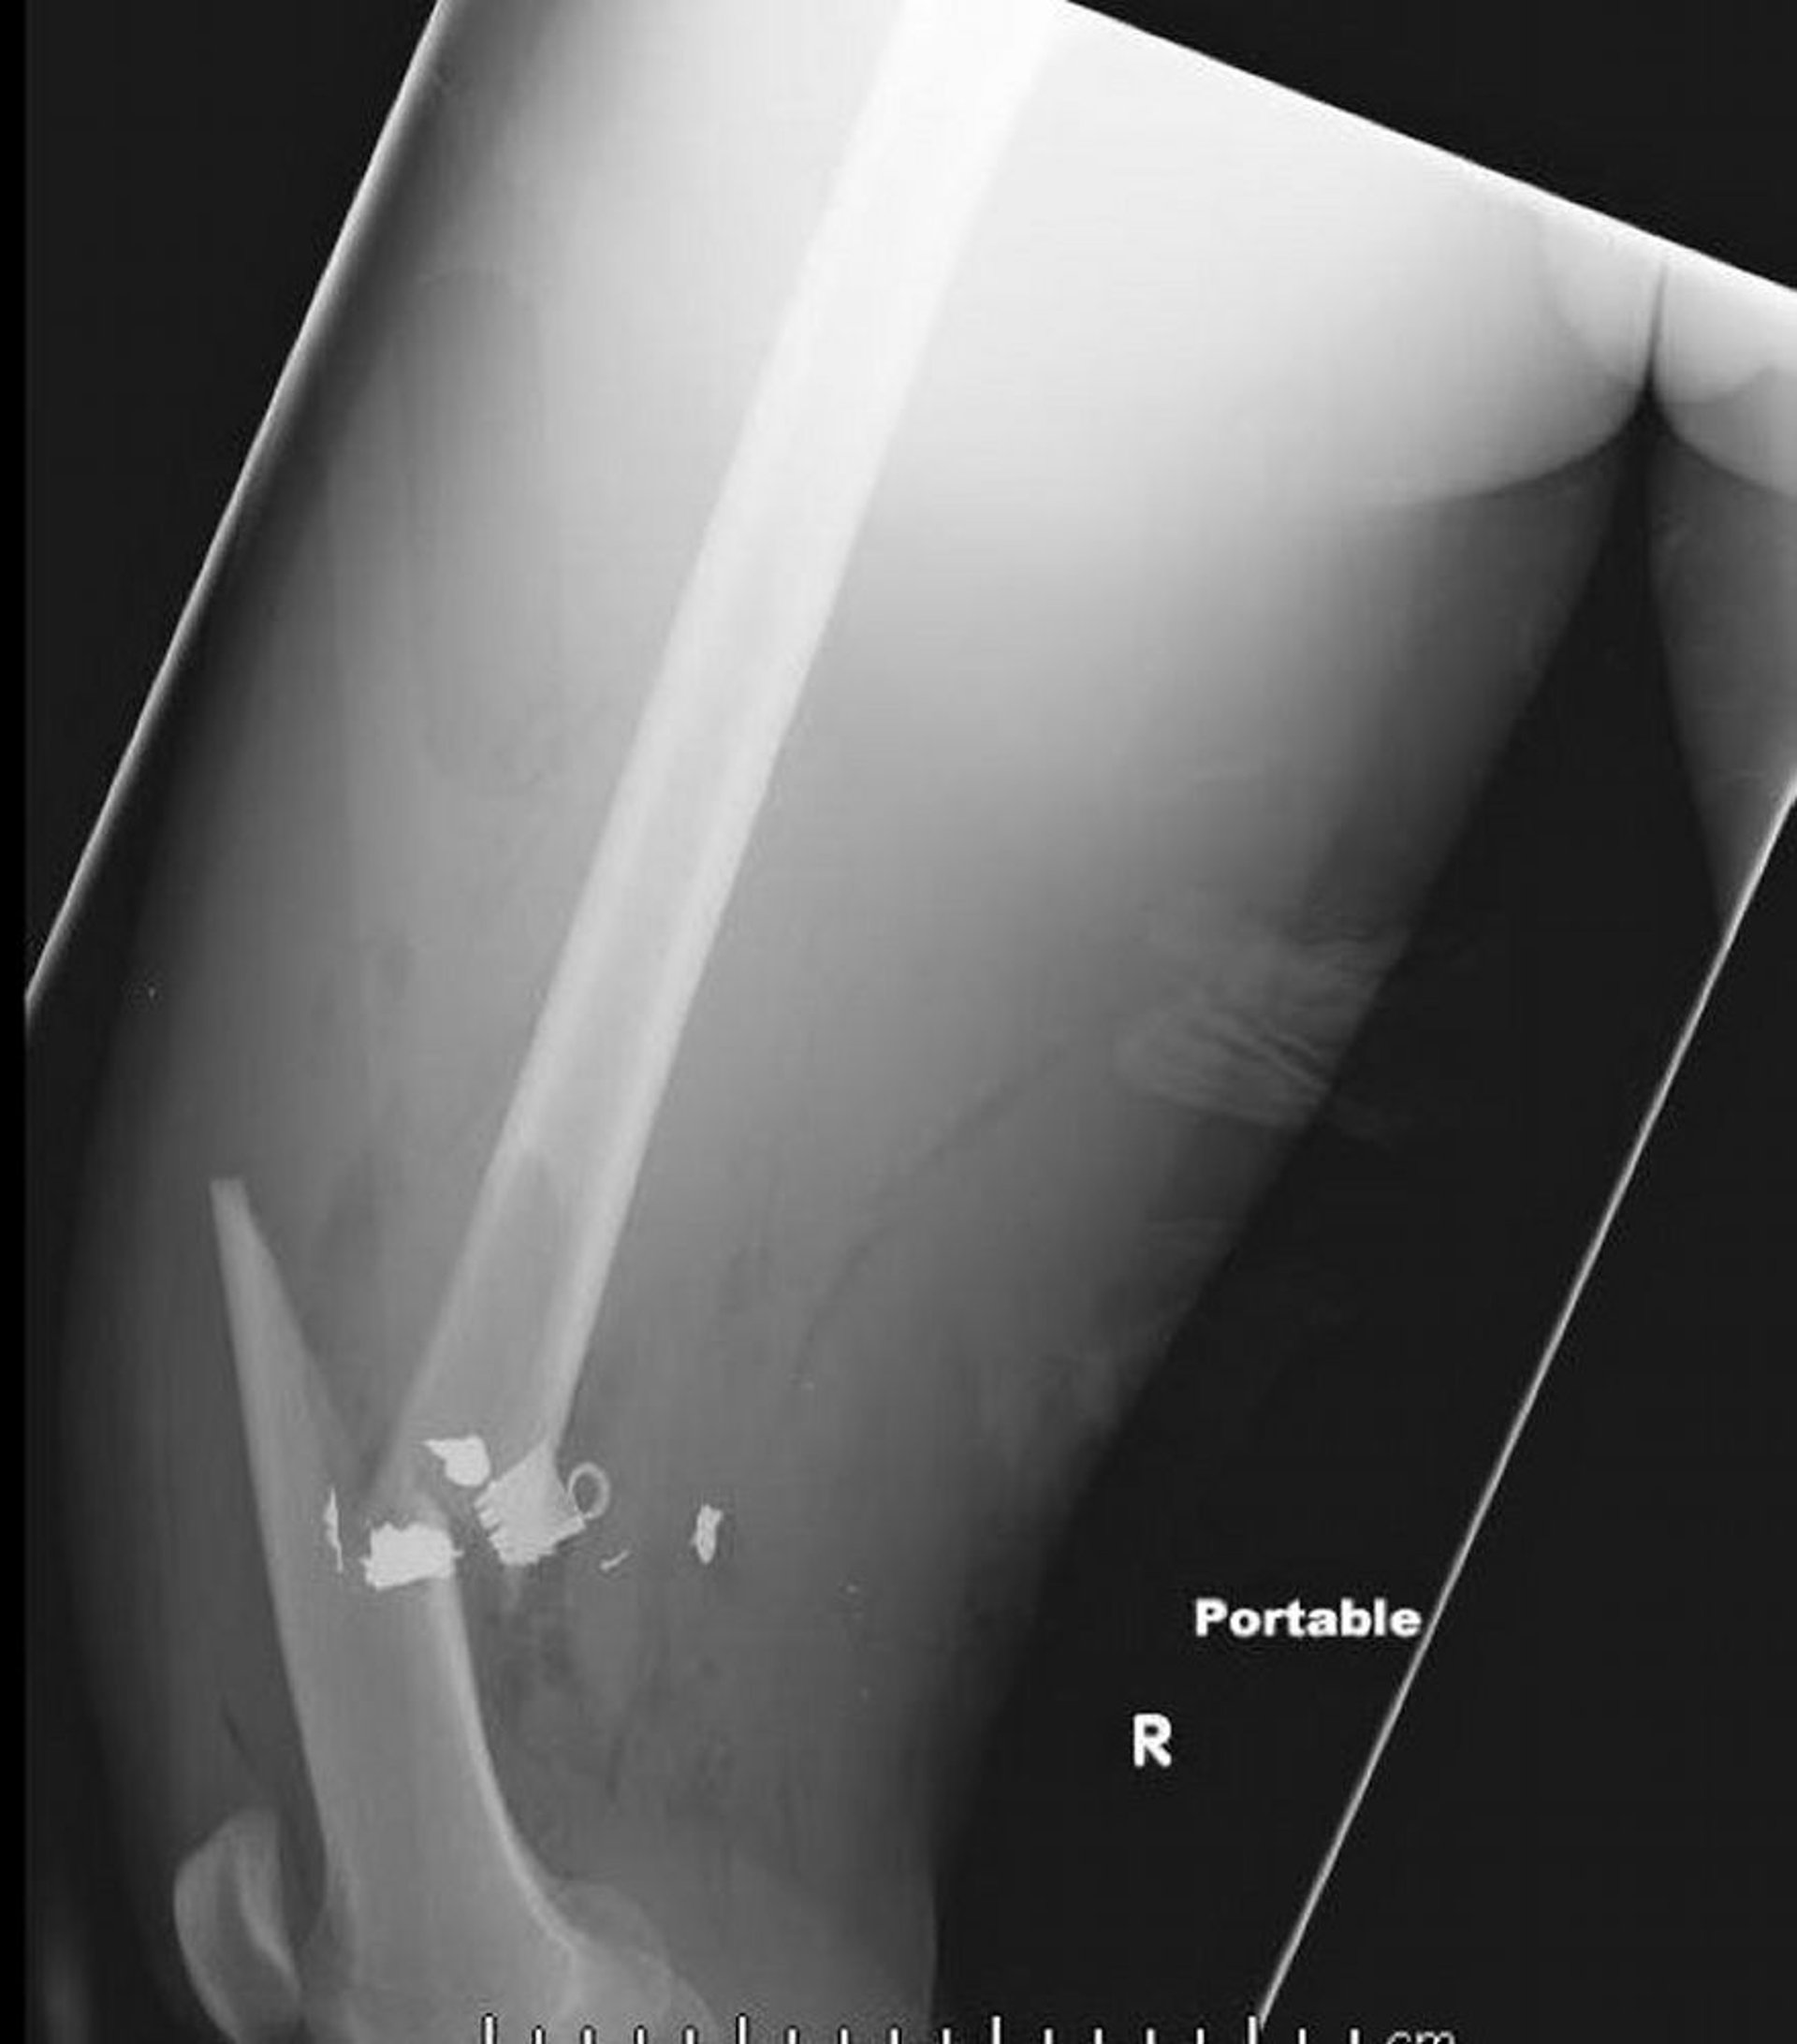

Frattura mediale della diafisi femorale (2)

Questa radiografia di profilo del femore mostra una frattura mediale della diafisi femorale con aria nei tessuti molli e corpi estranei di densità metallica trattenuti.